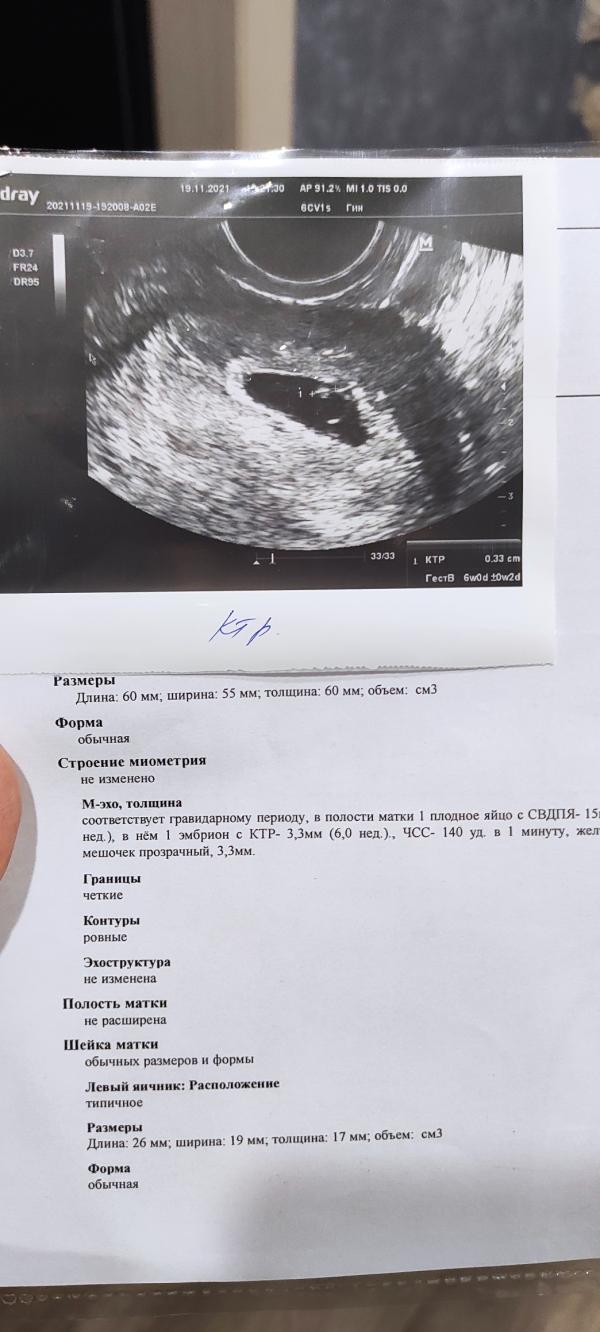

Эмбриончик на месте, ктр 3,3; 140уд/мин. Сегодня срок ровно 6 недель, всё хорошо и соответствует сроку. До сих пор не верится, что это чудо случиллсь со мной ☺